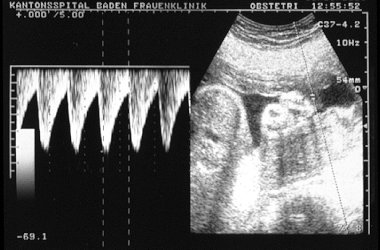

Doppler-Ultraschalluntersuchung

Die Doppleruntersuchung zeigt den Blutfluss z.B. in der Nabelschnur. Zudem können Flusskurven gemessen werden. Dadurch können Kreislaufbesonderheiten beim Ungeborenen erkannt werden. Mit dieser Methode können Risikoschwangerschaften (z. B. beginnende Mangelentwicklung des Feten, Hochdruckerkrankungen in der Schwangerschaft, Mehrlingsschwangerschaft) überwacht werden.